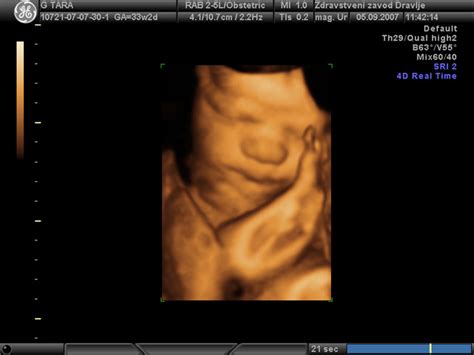

Merjenje nuhalne svetline (NT) je neinvazivna ultrazvočna preiskava, ki se prav tako izvaja v prvem trimesečju nosečnosti, med 11. in 14. tednom. Nuhalna svetlina predstavlja nabiranje tekočine na področju zatilja ploda. Povečana debelina nuhalne svetline je lahko povezana z večjim tveganjem za kromosomske nepravilnosti, kot so Downov sindrom, Edwardsov sindrom (trisomija 18) in Patau sindrom (trisomija 13), pa tudi z drugimi razvojnimi nepravilnostmi, vključno s srčnimi napakami.

Meritev nuhalne svetline se običajno opravi skupaj z oceno drugih parametrov ploda, kot so debelina plodove glave (BPD), dolžina plodove glave od temena do trtice (CRL) in srčni utrip ploda. Ti podatki, skupaj z materino starostjo, se vnesejo v poseben računalniški program, ki izračuna individualno tveganje za kromosomske nepravilnosti.